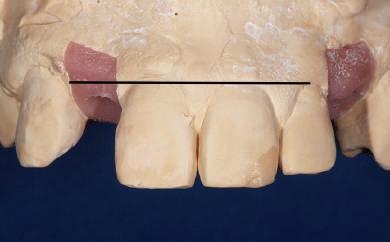

Dacă însă implanturile sunt plasate prea vestibular sau prea superficial, componentele nu permit un design adecvat al bontului, pentru că plasarea marginii este limitată iar conturul facial şi proximal poate fi compromis (fig. 1, 2).

Figurile 1, 2. Compromisurile conturului vestibular şi proximal sunt evidente. Implantul este la nivel tisular, tehnicianul neputând gestiona plasarea marginii sau a profilului intrasulcular pentru a îmbunătăţi estetica. Dacă se concepea un design tradiţional cu hexagon extern, marginea restauratoare s-ar fi putut plasa foarte aproape de interfaţa bont-implant, cu gestionarea mai bună a spaţiului.